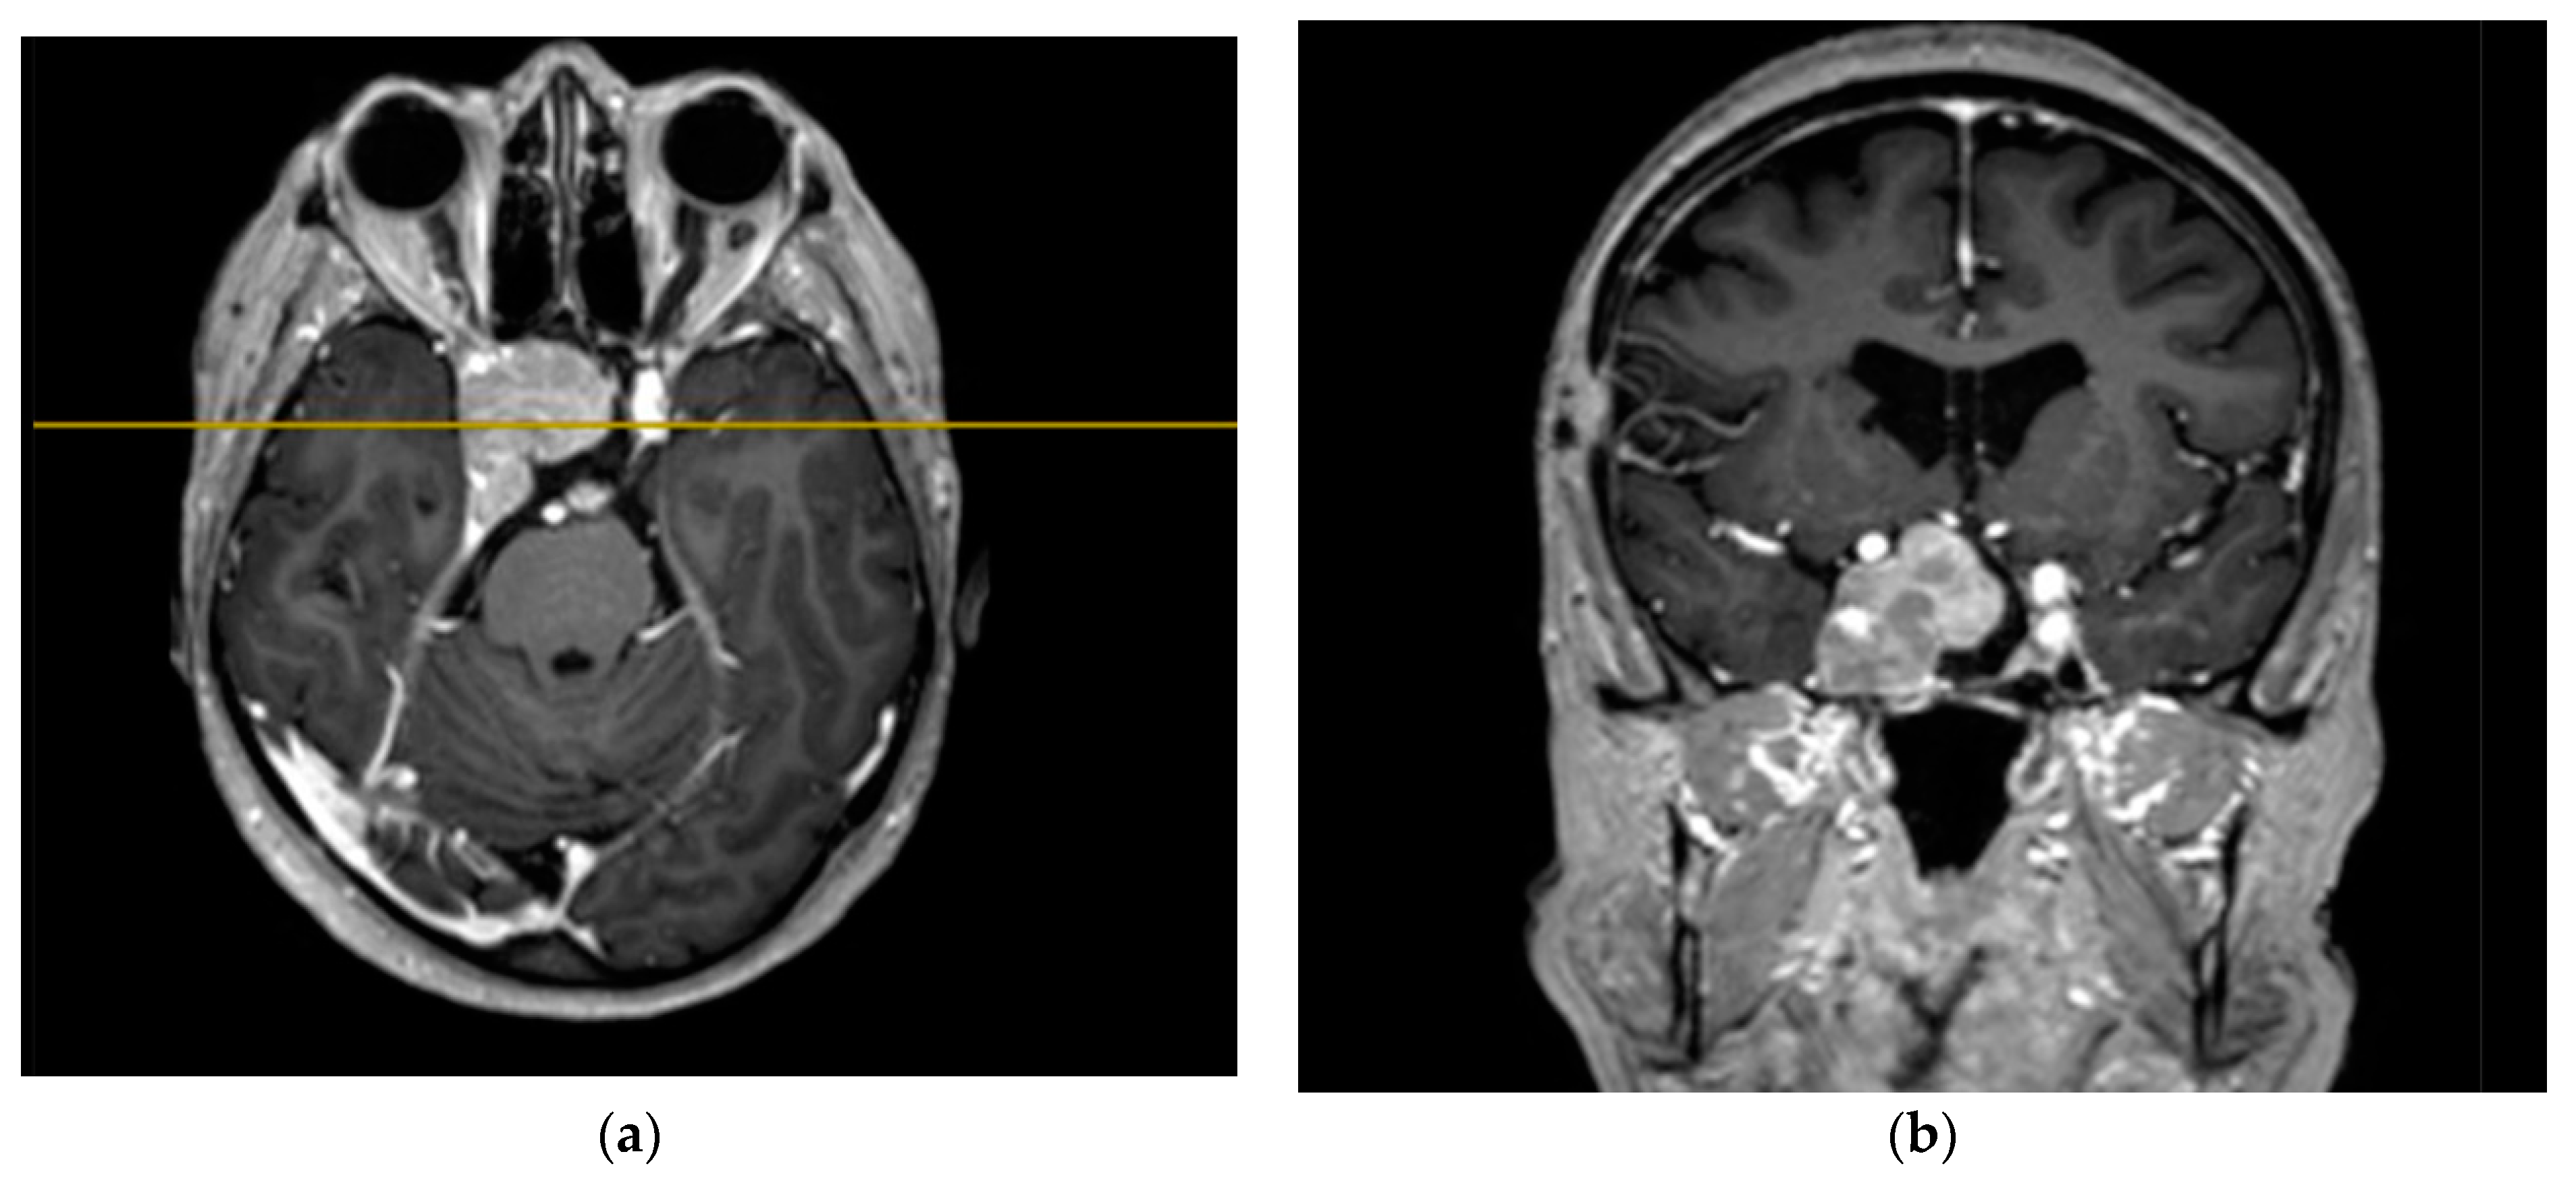

2.3. Clinical Part

The study’s clinical part involved 3 patients. Patients 1 and 2 were diagnosed with hormonally inactive pituitary macroadenomas, and patient 3 with a hormonally active one. All patients underwent endoscopic transnasal removal of the tumor at A.I. Evdokimov Moscow State University of Medicine and Dentistry. Two patients (1, 2) included in the study had previously undergone surgery with resection of the tumor at different times and had continued tumor growth. After the initial intervention, according to the histological examination, patients were diagnosed with PA, while Patient 3 had a primary PA. Additionally, at the preoperative stage, the infiltrative nature of tumor growth into the surrounding tissues was assumed. All patients were admitted to the clinic in satisfactory condition, without focal neurological symptoms. Patients 1 and 2 of the concomitant diseases had hypertension, and Patient 3 had secondary hypothyroidism. Patients 1 and 2, both in the preoperative period and after the surgery, took hormone replacement therapy for hypopituitarism: hydrocortisone and desmopressin. Patient 3 was taking L-thyroxine for a concomitant disease. None of the patients, either in the preoperative period or after the surgery, took chemotherapy drugs, since at the moment they are not included in the standard of treatment for patients with pituitary adenomas, given the benign nature of these types of tumors. All patients underwent a study of the hormonal profile and MRI of the brain with contrast enhancement with an assessment of the tumor spread and its interaction with the main nerve structures (Figure 3, Figure 4 and Figure 5). The patients’ primary characteristics are presented in Table 1.

Figure 5. Preoperative MRI images of Patient 3: (a) T1 image with contrast, axial projection, supralaterosellar tumor fragment, and (b) T2 image, frontal projection, endosuppralaterosellar mass with chiasm compression.